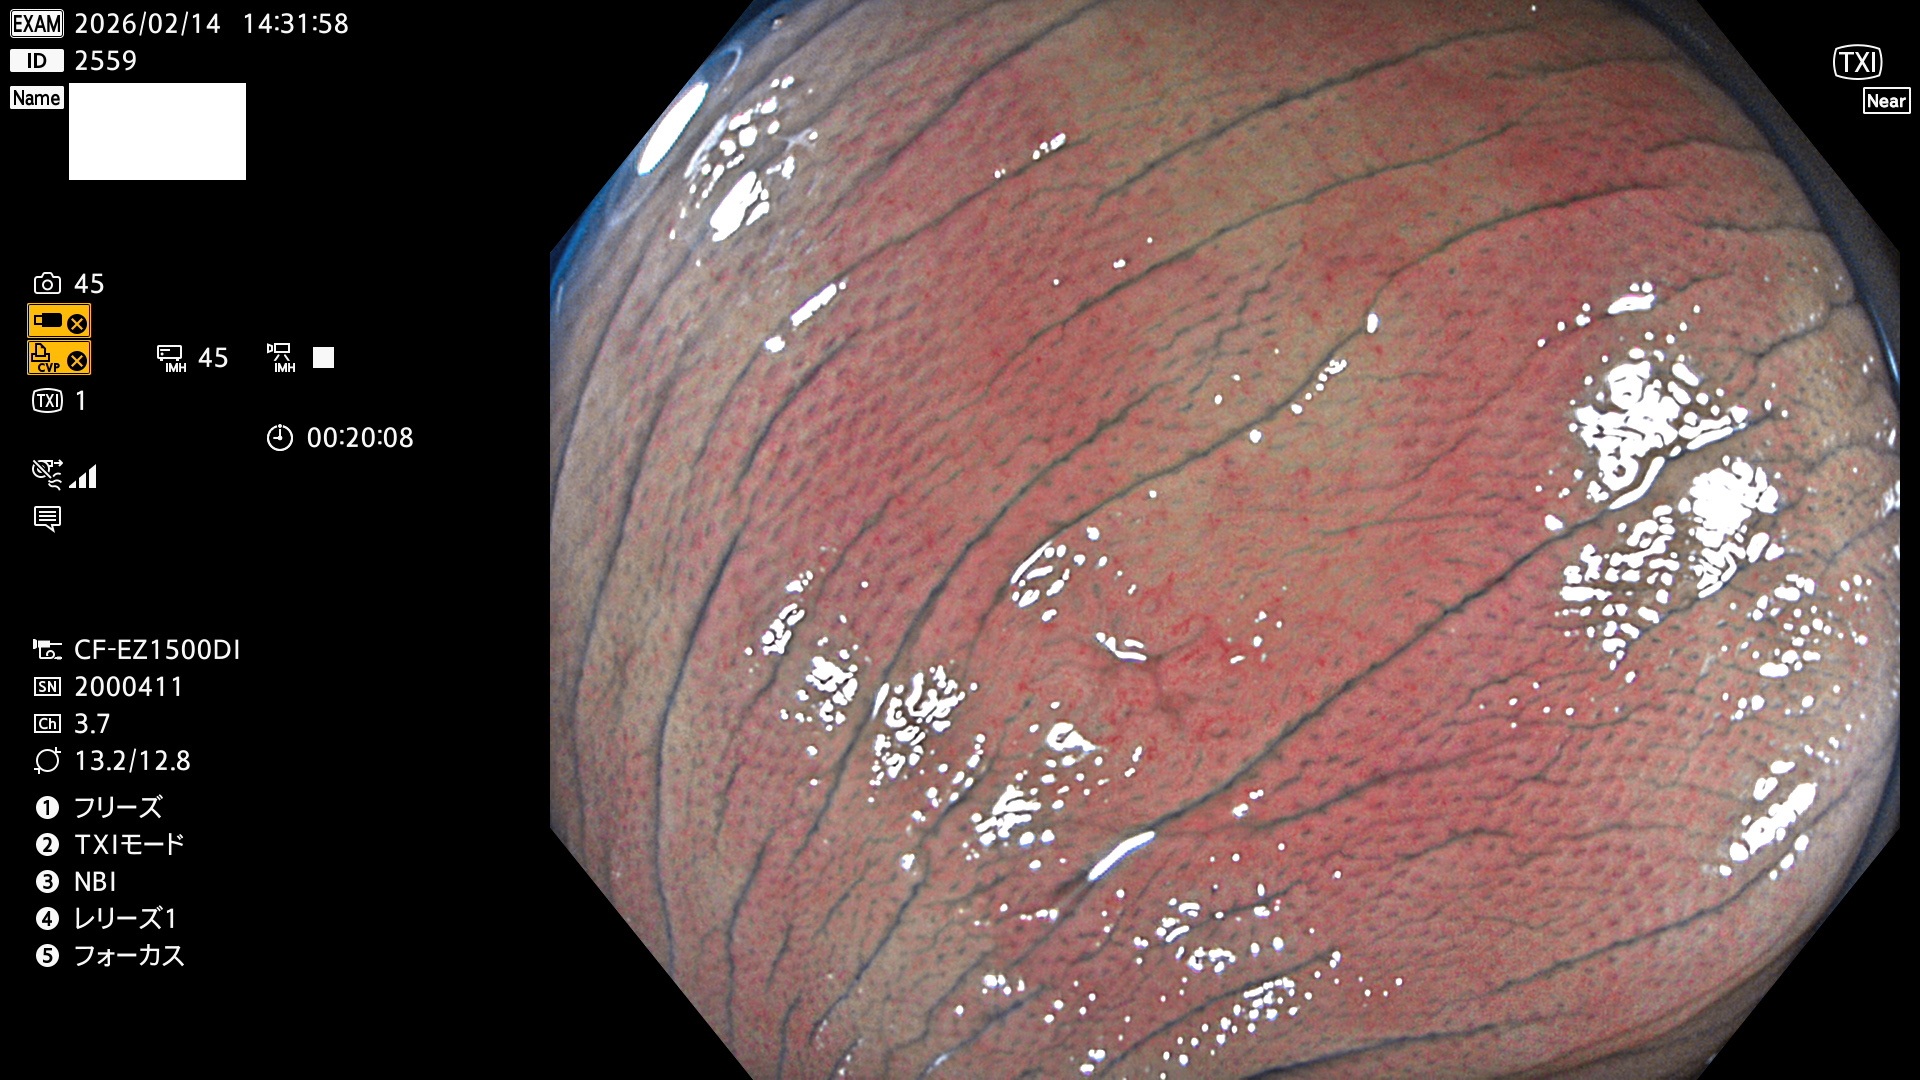

毎週の検査(木・金・土・日)に発見されたUbとUc型・腺腫を、その週の日曜の夜にUPし1週間、提示します。

2026年2月12日〜2月15日の4日間(40件)5個 (Uc_ADR=5個/40人=13%)